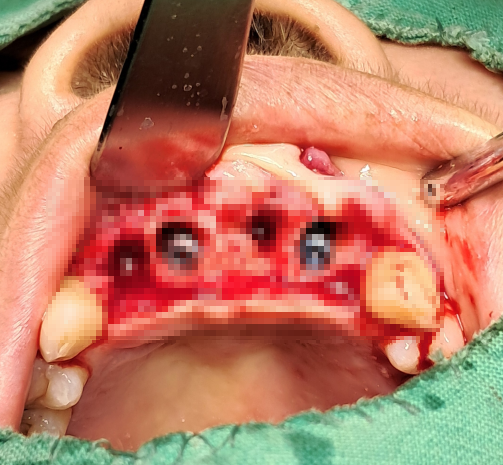

수술 중 소견

수술 중 확인된 상악 전치부는

* 협측 골의 부분적 소실

* 치조정 폭 감소

* 연조직 탄성 저하

등이 관찰되었으며,

식립 각도와 깊이에 대한 세밀한 조정이 필요했다.

임플란트는

잔존골을 최대한 존중하는 위치에 식립하였고,

과도한 전진이나 무리한 고정력 확보는 지양하였다.